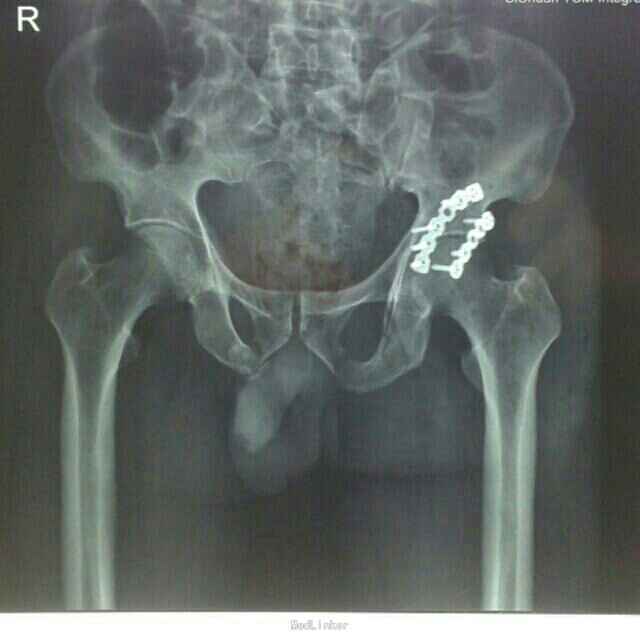

诊断:1、重物挤压伤 2、左髋臼骨折合并髋关节后脱位 3、骨盆粉碎性骨折 4、左股骨头骨折 治疗:患者入院后,予以完善术前检查,药物消肿、止痛、止血、补充血容量、保护胃粘膜及预防血栓形成等对症支持治疗,急诊在局部麻醉下行了“左髋关节脱位手法整复+左股骨髁上骨牵引”术,纠正髋关节后脱位及骨折错位畸形, 减轻髋关节压力,降低股骨头坏死的发生几率;经牵引治疗1周后,患者左髋关节弹性固定畸形及左下肢内旋、内收畸形纠正;复查牵引后DR及CT回示:左髋关节脱位已经纠正,骨折错位明显改善,完善相关检查及术前准备在"全身麻醉"下行了"骨盆粉碎性骨折切开复位钢板螺丝钉内固定+同种异体骨植骨+左胫骨结节骨牵引术"。术中见:左侧髋臼顶部及后侧壁骨折,呈粉碎性,后侧骨折线自髋臼上缘3.0cm处向后下走形,连接左侧坐骨支,向外后移位改变,左股骨头向后上脱位不稳,左侧髋臼顶部骨块向外上翻转移位,左髋臼内顶及后壁及股骨头见部分软骨挫伤、凹陷、瘀血,关节腔内见多枚细小骨碎片,关节腔及骨折断端见部分关节囊及软组织嵌顿。术后予患肢继续左下肢胫骨结节骨牵引制动,结合药物静滴预防感染、消肿、止痛、止血、改善血循环等处理,并指导患者行患肢主动功能锻炼;术后2周伤口愈合拆线,住院40天好转出院。

随访:患者出院后,定期门诊复诊治疗。 讨论:髋臼骨折,合并股骨头脱位者,因创伤严重,血运破坏,极容易发生股骨头缺血性坏死。手术时机,治疗方案、门诊随诊及功能锻炼方式、负重时间等都很重要。